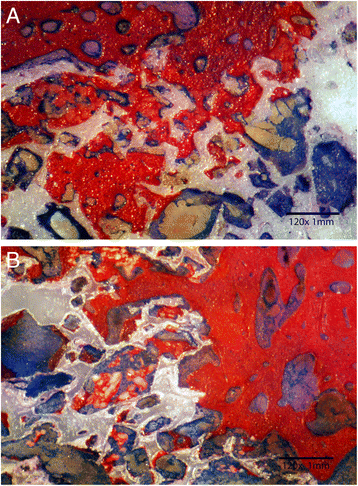

Histomorphometric analysis revealed that hydroxyapatite-enriched scaffolds had significantly (F = 14, P < 0.02) higher amount of new bone formation (33% ± 14) compared to the controls (21% ± 11). Amount of new bone formation was calculated as a percent of the total pore volume measured on each image. New bone growth started by lining pore cavity and propagated to gradually fill the entire pore volume (Fig. 2a). Bone ingrowth proceeded from the periphery of the scaffold and propagated towards its center (Fig. 2b). The surface under the guided tissue membrane was filled with unmineralized connective tissue. Regional areas of entrapped hydroxyapatite were observed inside the pore cavity of the enriched scaffolds (Fig. 2b). Entrapped islands of hydroxyapatite were surrounded by mineralized tissue. Lower amount of mineralized bone was observed for uncoated scaffolds (Fig. 3a, b).

Fig. 2

a Histological section demonstrating new bone growth (white arrow) in HA-enriched zirconia scaffold (black arrow). Unmineralized bone stained blue. Almost entire surface porosity was filled with new dense bone. b Histological section demonstrating bone growth in HA-enriched zirconia scaffold starting from the periphery of the surgical wound (white arrow). Islands of entrapped HA particles were surrounded by mineralized boney matrix (black arrow) which were identified using EDX

Fig. 3

a Histological section demonstrating bone growth in control zirconia scaffold (white arrow). Mineralized bone formation (black arrow) was less dense compared to HA-enriched scaffolds. b Histological section showing different sizes of pores present in porous zirconia scaffolds (Control specimen). Mineralization started by lining pore walls (white arrow). Unmineralized bone stained blue

Histomorphometric analysis revealed that bone growth start to develop as early as 6 weeks by lining pore cavity walls. Mineralized bone matrix was observed to penetrate 1–2 mm under the surface of the scaffolds thus providing mechanical stability of the inserted prosthesis. Healing continued by filling the entire pore volume (Fig. 2a, b). The presence of nano-hydroxyapatite particles enhanced bone growth and deposition compared to uncoated surfaces (Fig. 3a, b). Hydroxyapatite enhanced osteogenesis ability of zirconia scaffolds, and the proposed hypothesis was accepted.